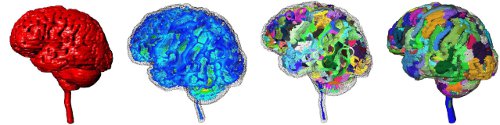

Shape understanding and modeling is a central task in biomedical imaging and associated applications. We present the latest developments in modeling 3D biomedical data via the Medial Scaffold (MS), a 3D acyclic oriented graph representation of the Medial Axis (MA). Both can be computed as the result of the singularities of a geometric wave propagation simulation.

We consider here some of the potential applications of this shape model in the realm of biomedical imaging. We can reconstruct complex object surfaces and make explicit the coarse-scale structures, which are ready-to-use in a number of practical applications, including: morphological measurement for cortex or bone thickness, centerline extraction (curve skeleton) for tracheotomy or colonoscopy, surface partitioning for cortical or anatomical surface classification, as well as registration and matching of shapes of tumors or carpal bones.

The MS permits to automatically and efficiently map an unorganised point cloud, i.e., simple 3D coordinates of point samples, to a coherent surface set and associated approximate MA. The derived MS is used to further recover significant medium and large scale features, such as surface ridges and main axial symmetries. The radius field of the MS provides an intuitive definition for morphological measurements, while the graph structure made explicit by the MS is useful for shape registration and matching applications.